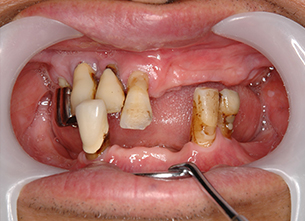

症例1 : 上下顎無菌顎症例

69歳、男性。

• 上顎は両側サイナスリフトと同時に即時荷重を行った。

• 下顎は抜歯即時埋入即時荷重を行った。

• 最終補綴物は、チタンのP.I.B.とM.B.のコンビネーションで修復した。

• 本症例の要旨は第39回日本口腔インプラント学会(大阪)にて症例報告した。